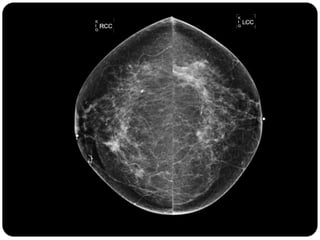

Paciente femenina de 66 años con historia clínica de 1er gesta antes de los 30 años y antecedentes de lactancia positiva, presenta una lesión palpable en la mama derecha. Los estudios radiológicos indican un diagnóstico de bi-rads 5, con biopsias revelando adenocarcinoma lobulillar infiltrante en la glándula mamaria derecha y adenocarcinoma ductal in situ en la izquierda. El caso fue evaluado por las doctoras Jacqueline Preciado Vargas y Beatriz E. González Ulloa.